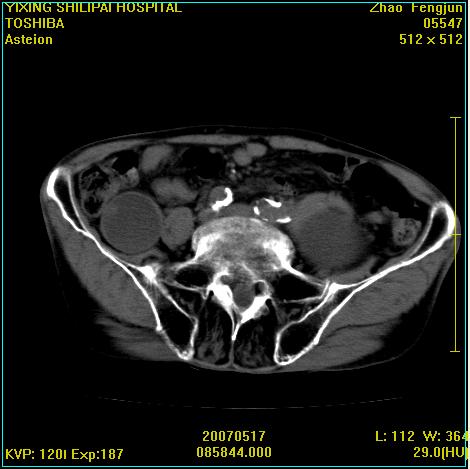

考虑:1、左侧腰大肌囊实性占位性病变(囊性神经根鞘瘤?);

2、右侧兰尾区囊性占位性病变(兰尾囊肿?囊腺癌?类癌?)

以下是引用xiaoniu在2007-5-26 10:45:00的发言:[br]腰大肌的病变应该没有问题,增强扫描还有轻度强化及细小血管影入内,应该排除脓肿,考虑占位性病变,腰大肌的占位多考虑:神经源性肿瘤。另外腹主动脉下端有真假腔的强化,考虑:主动脉夹层。[br][br][本贴已被 xiaoniu 于 2007-5-26 10:46:39 修改过]

以下是引用老爱克斯新网客在2007-5-26 18:26:00的发言:[br]1左下腹囊实性占位肿块,增强后不均匀强化,位于脊柱旁,椎体骨质无破坏软组织无肿胀,考虑神经源肿瘤神经鞘瘤可能大,2右下腹囊性占位性病变,增强后囊壁强化,考虑阑尾囊肿或囊腺瘤,